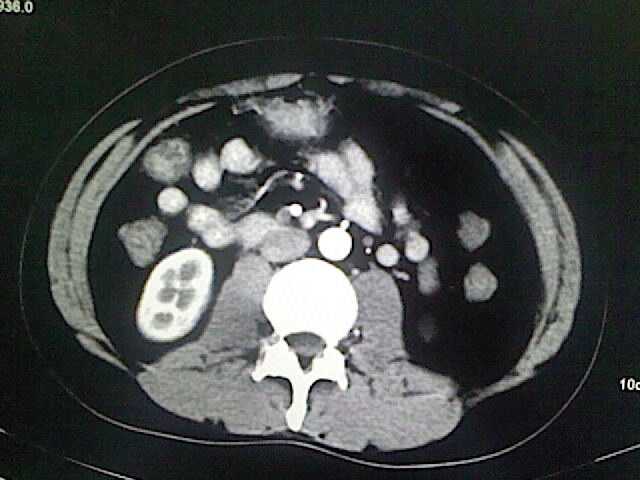

以下是引用卜一在2009-3-14 9:49:00的发言:[br]胆囊萎缩,胆囊壁不规则增厚,内部结构模糊,增强明显强化。另:肝左叶外侧段肝囊肿。支持:慢性胆囊炎!高度可疑:胆囊癌!

以下是引用余辉在2009-3-14 8:48:00的发言:[br]1)慢性胆囊炎。2)肝左叶外侧段肝囊肿。3)脂肪肝。[br]支持,胆囊萎缩,密度增高,不知b超具体有何提示,钙胆汁?结石?

以下是引用jiangjing在2009-3-14 10:18:00的发言:[br]1)慢性胆囊炎。2)肝左叶外侧段肝囊肿。3)脂肪肝。4.】建议行肝功能检查